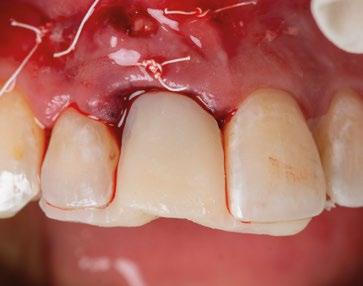

15.- Cortamos pilar provisional y adaptamos el TempShellTM con composite. Podemos comprobar la predictibilidad en cuanto a la posición 3D planificada de nuestro implante. (Figuras 30 a 32)

16.- Colocamos restauración provisional atornillada y fuera de oclusión y traccionamos hacia coronal de los tejidos. (Figura 33)